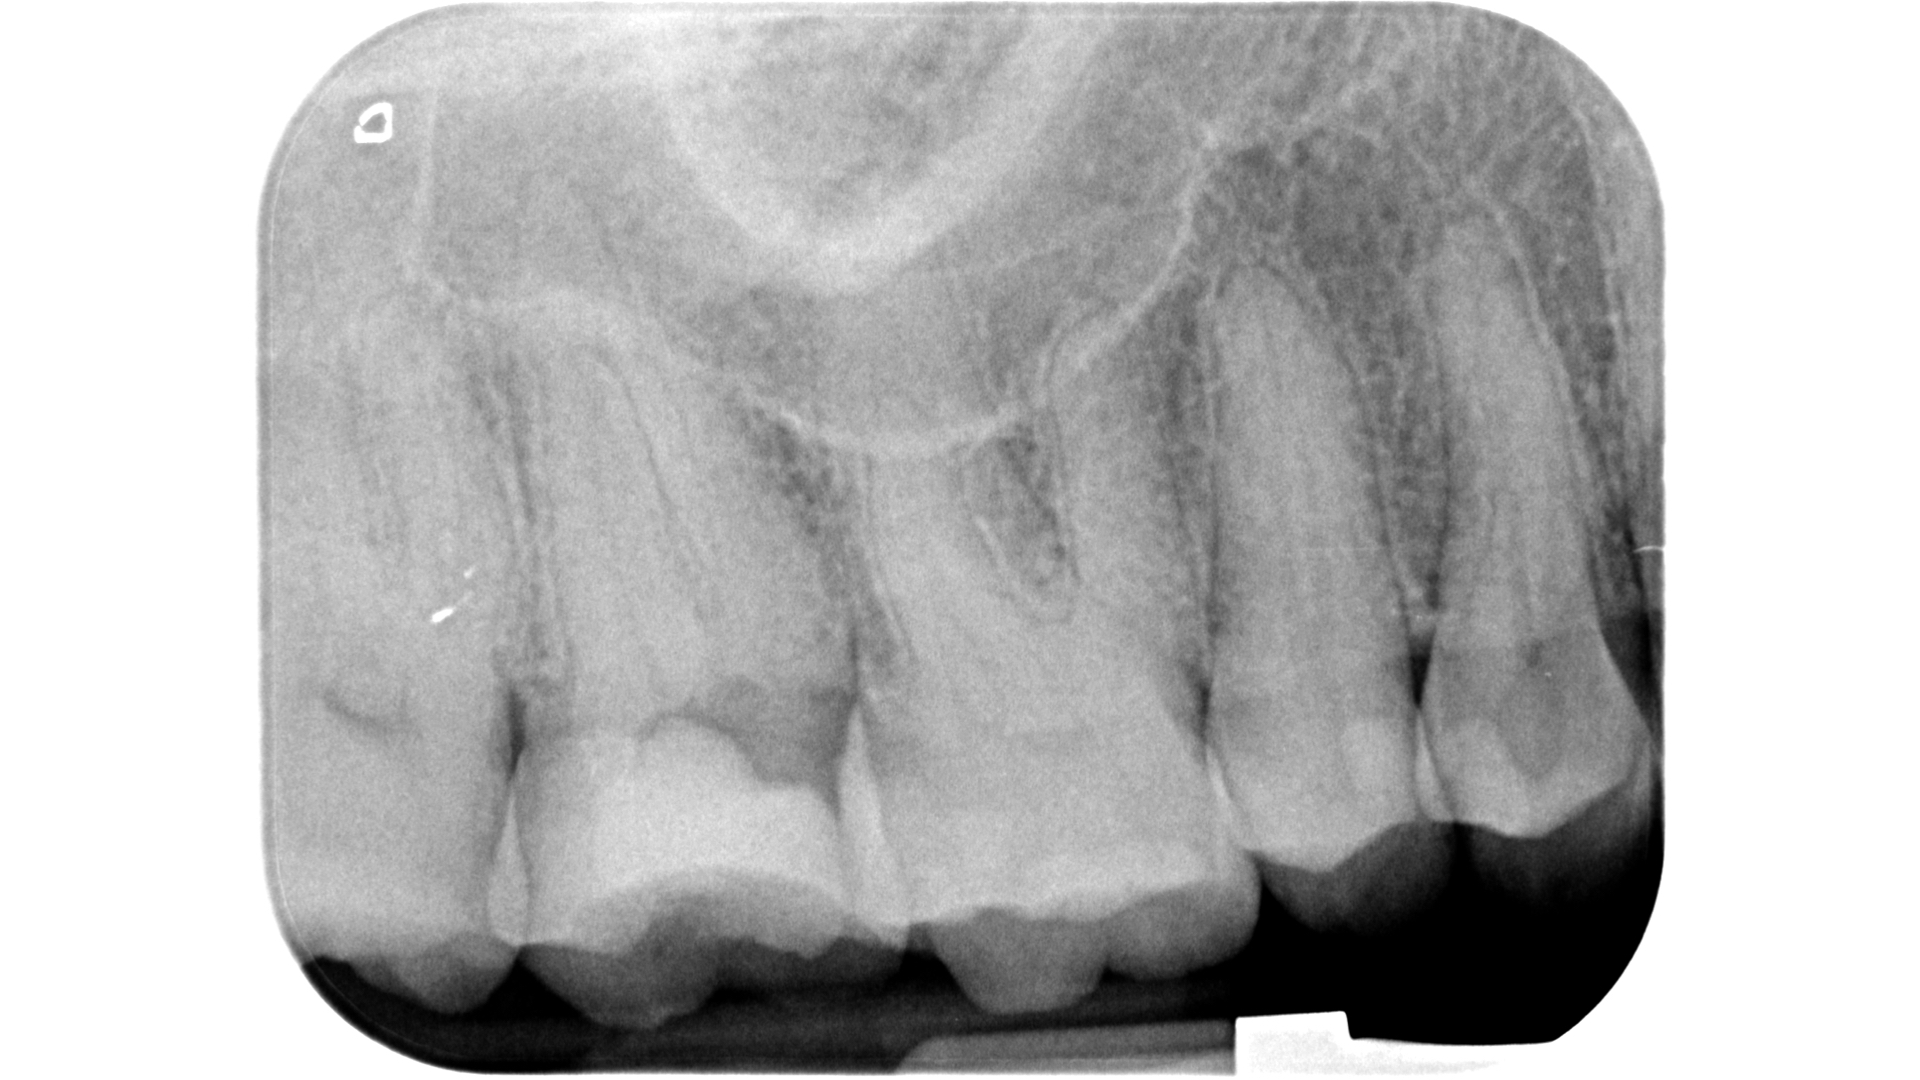

Fig. 1: Pre-op radiograph of a maxillary molar undergoing emergency treatment at another practice.

An inadequate access cavity in terms of position, depth and extension can lead to complications in the subsequent phases, making it impossible to locate the canal orifices, overstressing the mechanical nickel–titanium (NiTi) files or weakening the residual dental structure (Figs. 1–5). While, in the past, there was a tendency to emphasise the importance of a large access cavity that would allow the insertion of manual and mechanical instruments following the main axis of the canal, in recent years, the proposal of minimal access cavities defined in various ways (“ultra-conservative cavity”, “ninja cavity”, “truss access cavity”)4 has become predominant.